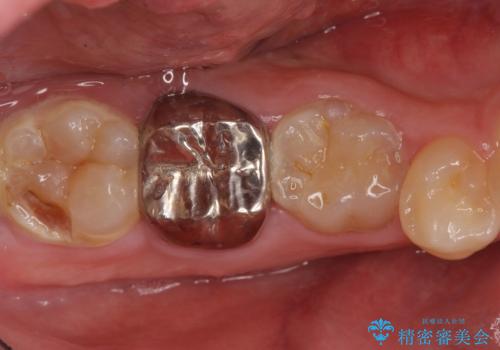

- 口の中を予算の範囲内でできるだけきれいにしたいとのことで来院された患者様です。

矯正治療と虫歯治療を組み合わせてご提案しましたが、ご予算との兼ね合いで虫歯治療のみを行うこととなりました。

奥歯は十分な歯の高さがなかったため、クラウンをかぶせる前に歯周外科治療で歯の高さを出しています。

歯科に通うようになってから磨き残しの状態も改善されていきました。